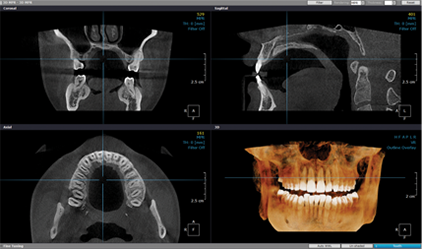

3D CT 진단

상악동 해부학적 구조 분석 및 수술 계획 수립